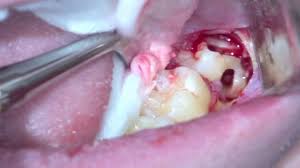

How much does it cost to have wisdom teeth removed? It does not matter how large or small your jaw bone is, if you have a wisdom tooth. Almost all dental insurance schemes cover up to 40 to 60 percent of the total cost of removing the cost of extracting a wisdom tooth depends on the condition of the tooth and standard dental charges existing in a region or city. How can you tell if wisdom teeth are impacted or infected? Your wisdom teeth are the only teeth you grow as you enter your late teens or early twenties. In some cases if your dentist believes that your wisdom teeth aren't growing in correctly, he may suggest having them removed even before they become a problem. The question is, how much is that the good news is that most dentist's offices do offer some type of financing when it comes to things that cost this much. In most cases, wisdom teeth are removed before they erupt.

Signs that it's time to remove your wisdom teeth.